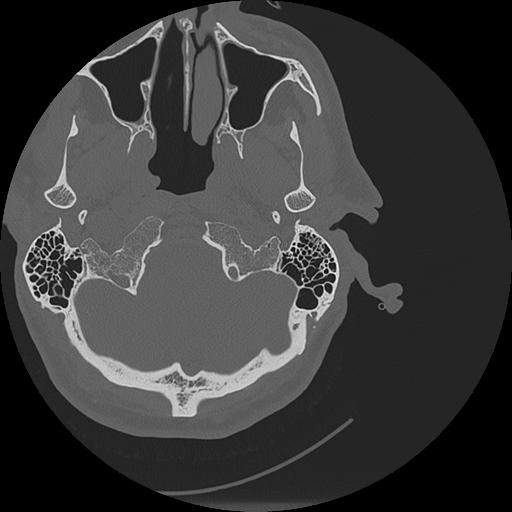

7 HUESO,,Vol,0.5,HUESO,,